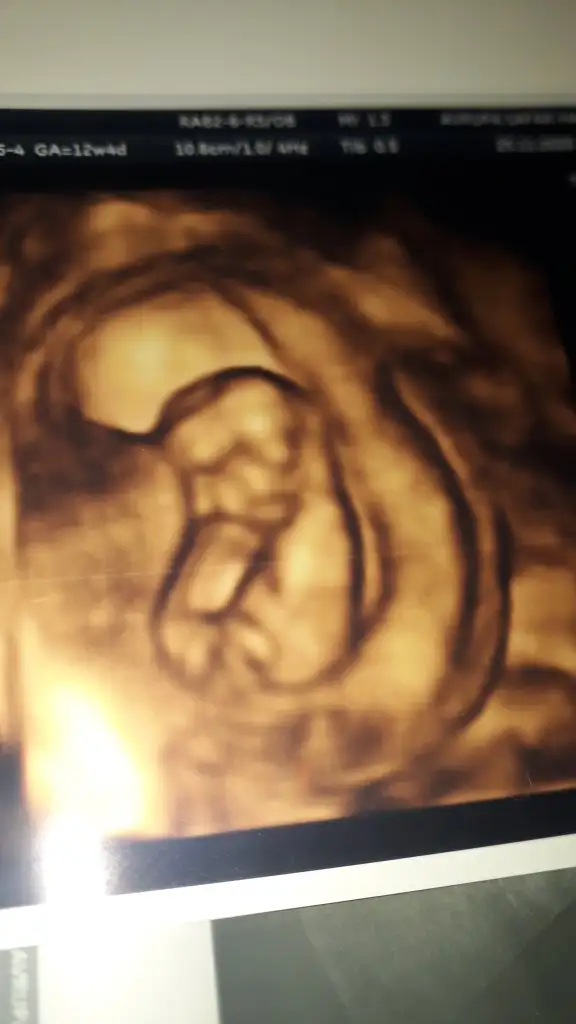

Erkek gibi emin olamadım karanlık USGMerhabaIkra meyra Bende bugün doktordaydim , 12+4 um. Ama cinsiyet belli değil dedi doktor. Sen bir tahminde bulunabilir misin ?

Ben ekranda bacak arasını gördüm, çok minicik bir cikinti vardi . Emin olamadım , erkek de daha fazla olması gerek diye düşündüm, acaba kizmi diye sevinecektimErkek gibi emin olamadım karanlık USG![]()